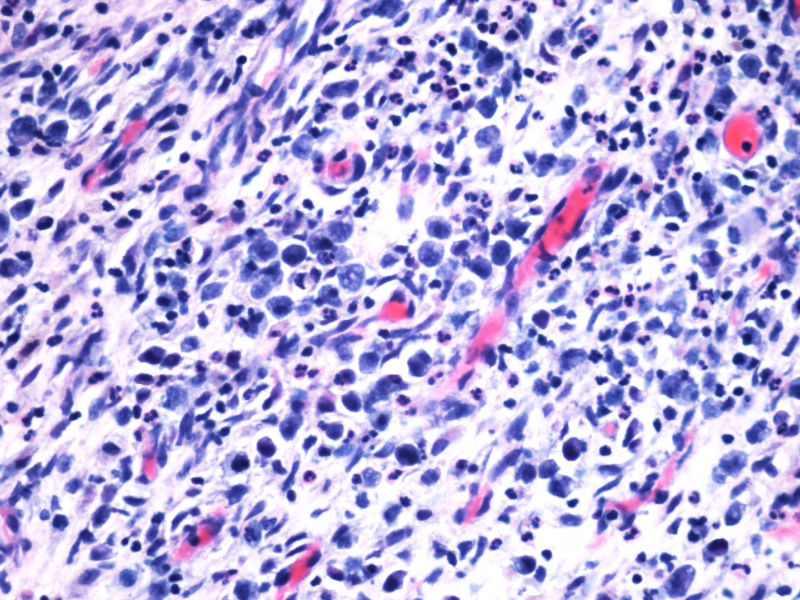

1. 支持CHL的方面: 本例CD15和D30,尤其是前者的表达强烈支持霍奇金淋巴瘤CHL,但似乎也不能完全排除ALCL;EMA-也支持CHL;

2. 支持ALCL的方面: 但CHL一般有更好的PAX5-表达;CHL的CD68一般不表达,而ALCL的KP1可以+但PGM1多-;CD3+细胞不多,可能是肿瘤细胞缺失了CD3的表达,如果再有CD5,CD4的结果就更好了;

3. 其他标记:如ALK, EBER, Oct-2, Bob-1, CD4,KP1,PGM1, ganzymeB, MUM1等对诊断也有帮助,另外也需考虑其他疾病。

本例患者未查见淋巴结肿大,无肝脾肿大。其余标记物:大细胞显示CD2,CD3,CD4,CD8,CD5,EMA,TIA-1,GranB, oct, Bob1, EBER均阴性。

阳性的有CD30,CD15,CD43,ALK,perforin。